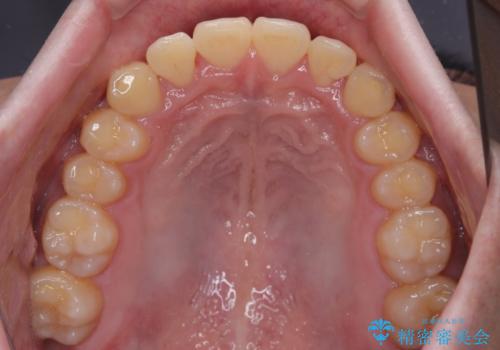

- 上下前歯の捻れやデコボコを気にして来院された患者様です。

マウスピース矯正でもワイヤー矯正でも対応可能でしたが、極力楽をして治したいとのことでワイヤー装置にて治療をおこなうこととしました。

口元はそれほど突出しておらず、患者様自身も気にしていらっしゃいませんでしたが、前歯の捻れやデコボコを解消すると、前方に拡大され、治療後に出っ歯仕上がりとなるリスクがあったため、補助装置により上顎臼歯を後方移動していくこととしました。